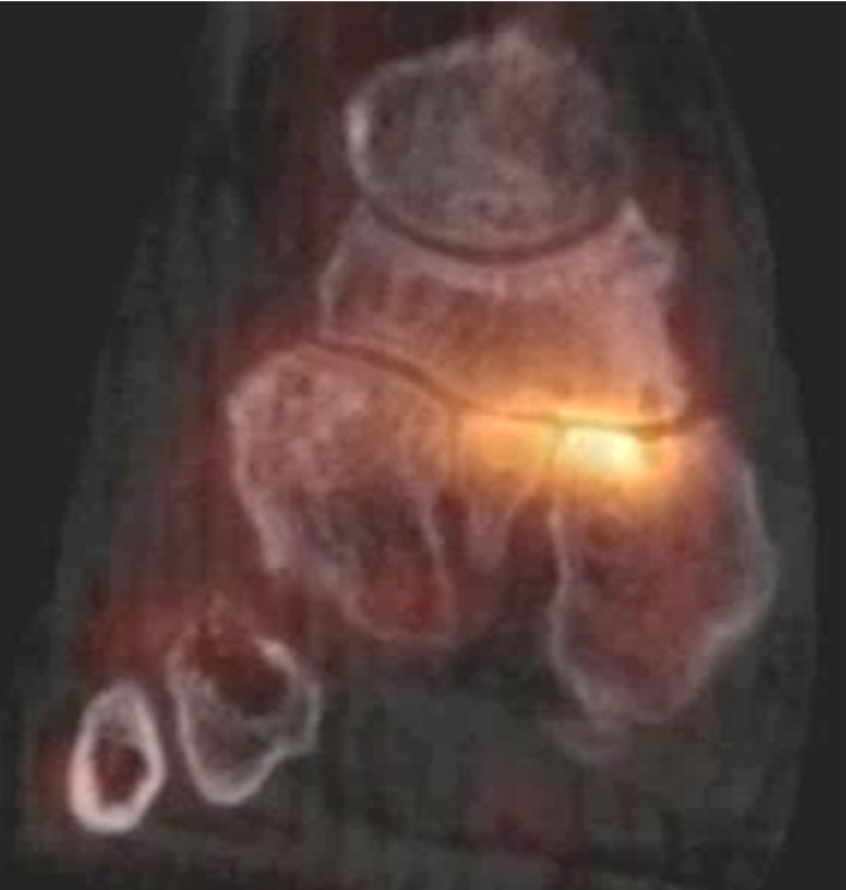

Gegebenenfalls muss die Osteomyelitis des Diabetischen Fußes von der Charcot-Neuroarthropathie differenziert werden. Die Charcot-Arthropathie betrifft primär die Tarso-metatarsalen Gelenke, sodass eine Destruktion von Knochen im Vorfuß primär verdächtig auf eine Osteomyelitis ist und gegebenenfalls bereits mit einer Standard-SPECT/CT diagnostiziert werden kann, wenn entsprechende CT-morphologische Veränderungen vorliegen.

SPECT/CT beim Diabetischen Fuß

Schätzungsweise 15-20 % der Diabetiker entwickeln im Verlauf ihrer Erkrankung ein Ulcus am Fuß 606162 und Ulcera sind die primäre Eintrittspforte für die Entstehung von Infektionen und Osteomyelitiden. In der Literatur sind bei optimaler Untersuchungstechnik Treffsicherheiten der Nuklearmedizinischern Diagnostik von Diabetischen Osteomyelitiden über 90 % beschrieben, was sowohl die Präsenz als auch die lokale Ausdehnung der Entzündung betrifft; hier hilft insbesondere die SPECT/CT dabei, zwischen knöchernem und Weichteil-Befall zu diskriminieren 6360.